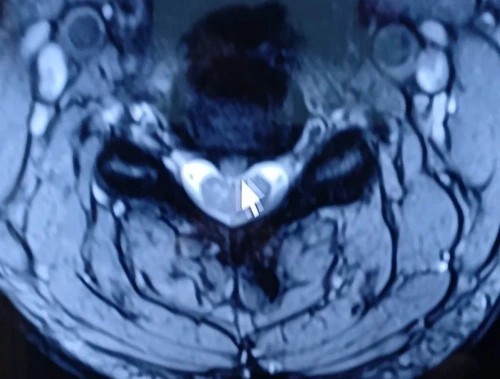

화면 중앙과 척추뼈의 단면 주변 구조물들이 하트처럼 보여서 한참을 신기하게 바라봤었다. 고통의 자리가 아니었지만 그런데 이상하게도 그 하트 모양이 마치 내 몸이 나를 위로하려는 흔적 같았다.

"아프지? 그래도 여기 있어."

‘여기가 신경근이 다 나가는 곳인가?'

하트를 멍하니 바라보며 나는 아주 잠깐, 아프지 않았다.